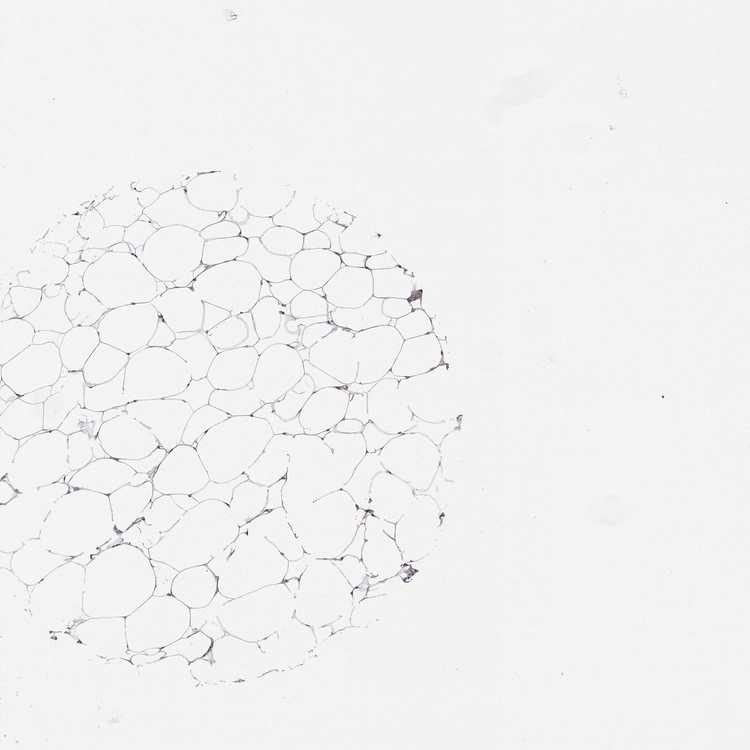

BREAST - Antibody stainingi

Antibody staining in the annotated cell types in the current human tissue is reported as not detected, low, medium, or high, based on conventional immunohistochemistry profiling in selected tissues. This score is based on the combination of the staining intensity and fraction of stained cells.

Each image is clickable and will lead to virtual microscopy that enables deeper exploration of all samples and also displays staining intensity scores, fraction scores and subcellular localization as well as patient and tissue information for each sample.

Antibody HPA074573

Adipocytes Not detected

Glandular cells Not detected

Myoepithelial cells Not detected